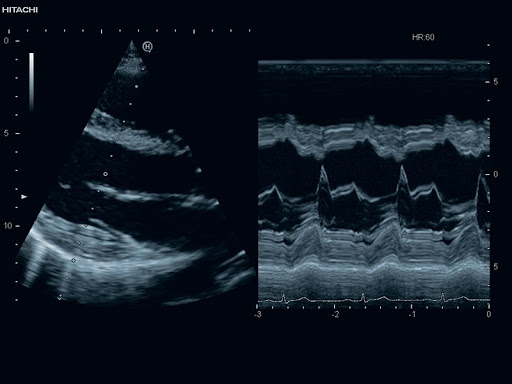

Рабочие режимы: B, B/B, M, B/M, трапециевидный режим

- Допплерография в режимах PW, B/PW, M/PW, B/M/PW, CW, B/CW, Fine Flow

Тканевый допплер (TDI)